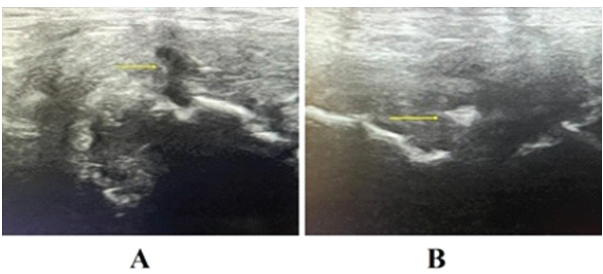

All subjects included in this study were treated with BTX-A infiltration at the level of the LA and RA, unilaterally or bilaterally, depending on the type of PPAC lesion observed. After an 8-week rehabilitation program, 90% of the treated subjects demonstrated, upon US assessment, complete anatomical healing of the PPAC injury (restitutio ad integrum). An example of the healing process observed in US is shown in Fig. 6.

Figure 6: US assessment of the healing process of a prepubic aponeurotic complex lesion. (a) shows the original lesion in longitudinal view before medical treatment (arrow). (b) shows the same lesion in axial view observed 4 weeks after medical treatment, showing signs of advanced healing (arrow).